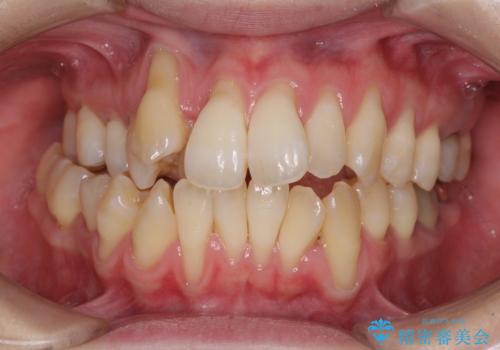

捻れて前に出ている前歯 ワイヤー装置での非抜歯矯正